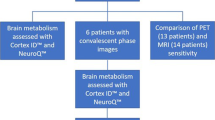

Study characteristics and a qualitative summary

Included studies were conducted in China (n = 7), USA (n = 4), Germany (n = 4), South Korea (n = 2), India (n = 1), Spain (n = 1), France (n = 1), Mexico (n = 1), and Denmark (n = 1). Among included cases, there were anti-LGI1 (n = 144), anti-NMDAR (n = 103), anti-GAD (n = 22), anti-GABA (n = 14), anti-VKGC (n = 23), anti-Hu (n = 9), anti-CASPR2 (n = 4), and anti-Ma2 (n = 2) (Table 1). There was no study of acute disseminated encephalomyelitis (ADEM) which met our eligibility criteria. The included studies were published between 2005 and 2021.